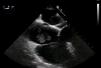

El uso de la ecocardiografía transesofágica (ETE) intraoperatoria permite detectar la migración de trombos a VCI y cavidades cardíacas (fig. 1, vídeos 1, 2 y 3) y apoya la decisión sobre la técnica quirúrgica y el modo de perfusión16.

La migración del trombo hacia el corazón durante la intervención puede tener consecuencias fatales si no se reconoce y se trata de forma precoz. Para evitar la embolización pulmonar, se han empleado en ocasiones filtros venosos, aunque su uso es controvertido. La ETE se utiliza para el diagnóstico precoz de esta complicación durante el procedimiento31 como método de monitorización continua que permite la visualización del trombo y evita las complicaciones hemodinámicas y la alteración en la relación ventilación-perfusión que puede ocasionar su migración32. En nuestra serie se monitorizaron con ETE los 11 pacientes con grado III y IV para evaluar de forma dinámica el compromiso intraauricular del tumor. No se observó en ningún caso la migración trombótica intraoperatoria.

Concluimos que el tratamiento quirúrgico de los tumores retroperitoneales con extensión a VCI se beneficia de un abordaje multidisciplinar. El uso de CEC es muy útil en los grados III y IV de Neves-Zincke, asociado incluso a la HCA para facilitar la resección del tumor. La ETE intraoperatoria confirma el nivel del trombo tumoral en la VCI y permite la detección de fenómenos embolígenos durante el acto quirúrgico. Esta cirugía consigue una supervivencia elevada a corto plazo, aunque la supervivencia a largo plazo está limitada por la evolución propia del tumor: es la infiltración de la pared de la VCI la que marca un peor pronóstico.